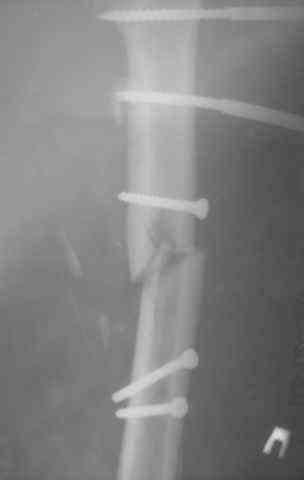

Несрошийся открытый фрагментарный,оскольчатый,перелом в/с/3 правого бедра |

Несрошийся открытый фрагментарный, оскольчатый, перелом в/с/3 правого бедра с размозжением мягких тканей. Состояние после ПХО,МОС,ВО ЧКФ стержневым АВФ. 10.10.09.Заживление раны per prima. Операция:16.12.09,открытый накостный МОС,аутокостная пластика(из крыла подвздошной кости)правого бедра. После п/о периоде заживление раны вторичным натяжением (на 5-е сутки распущены швы, после очищения раны наложины вторичные швы) На этапных RO-гр:остеолизис костного трансплантата и дистального фрагмента перелома бедра. Вопрос:дальнейшая тактика лечения-БИОС аутокостная пластика (трансплантат на сосудистой ножке М/Б кости). Билокальный остеосинтез по Илизарову с остеотомией подвертельной и надмыщелковой области бедра. Мозможен ли аутотрансплантат без сосудистой ножки? Чем улучшить васкуляризацию? Декортикация? Тактика выжидания остеолизиса, а затем оперативное лечение.